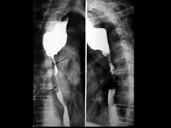

问题 男性,75岁,有陈旧性心肌梗死与肺气肿史,食道造影片示胸上段食管有4cm充缺,蕈伞型,中度梗阻,最佳方案为()

选项 A.手术治疗 B.术前放疗+手术 C.化疗 D.手术+术后放疗 E.根治性放疗

答案 E